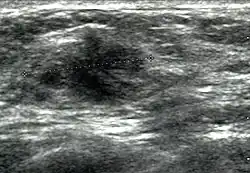

Die diagnostische Differenzierung durch die Sonographie geht heute über die Unterscheidung von zystischen von soliden Befunden hinaus, indem sie die soliden Läsionen in gutartige, wahrscheinlich gutartige, suspekte und hochsuspekte unterscheidet (BIRADS-Klassifikation). Hier sind besonders neben dem internen Echomuster (Echogenität) die Randstrukturen eines Herdbefundes von Relevanz.[11]